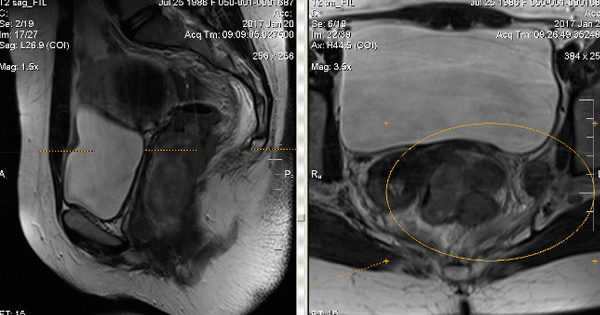

ΠΡΠ»ΠΈ Π΅ΡΡΡ ΡΠ°ΠΊΠ°Ρ Π½Π΅ΠΎΠ±Ρ ΠΎΠ΄ΠΈΠΌΠΎΡΡΡ, ΡΠΎ Π±ΠΎΠ»ΡΠ½ΡΠΌ Π½Π°Π·Π½Π°ΡΠ°ΡΡ ΡΠ°Π·Π»ΠΈΡΠ½ΡΠ΅ ΠΊΠΎΠΌΠΏΡΡΡΠ΅ΡΠ½ΡΠ΅ ΠΎΠ±ΡΠ»Π΅Π΄ΠΎΠ²Π°Π½ΠΈΡ. ΠΠΎΠΆΠ½ΠΎ ΠΎΡΡΡΠ΅ΡΡΠ²Π»ΡΡΡ ΡΠ»ΡΡΡΠ°Π·Π²ΡΠΊΠΎΠ²ΠΎΠ΅ ΠΈΡΡΠ»Π΅Π΄ΠΎΠ²Π°Π½ΠΈΠ΅, ΠΊΠΎΡΠΎΡΠΎΠ΅ ΠΏΡΠΎΠ²ΠΎΠ΄ΠΈΡΡΡ Π»ΠΈΠ±ΠΎ ΡΡΠ°Π½ΡΠ°Π±Π΄ΠΎΠΌΠΈΠ½Π°Π»ΡΠ½ΠΎ, Π»ΠΈΠ±ΠΎ ΡΡΠ°Π½ΡΡΠ΅ΠΊΡΠ°Π»ΡΠ½ΠΎ.

- ΠΌΠ°Π³Π½ΠΈΡΠ½ΠΎ-ΡΠ΅Π·ΠΎΠ½Π°Π½ΡΠ½Π°Ρ ΡΠΎΠΌΠΎΠ³ΡΠ°ΡΠΈΡ;